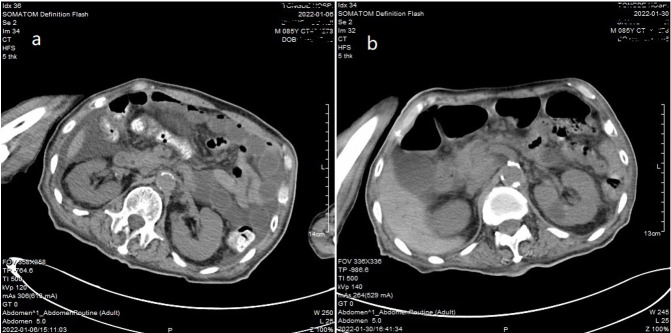

Case report: An 85-year-old man was admitted to the hospital with weakness and slow movement. Shortly after hospitalization, he experienced incomplete small bowel obstruction; thus, parenteral nutrition and intravenous esomeprazole were administered. When intestinal obstruction was relieved, the patient suddenly experienced seizure-like symptoms three times, and 24-h electroencephalogram did not capture any epileptiform pattern. After excluding other causes, we considered serum magnesium deficiency as a diagnosis. Low serum magnesium levels were related to a shortage of absorption due to small bowel obstruction, excess excretion of renal dysfunction, and the use of proton pump inhibitor. However, the exact mechanism underlying the hypomagnesemia-induced seizure-like activity remained unclear. After adjusting the nutritional support and magnesium supplementation, the patient's serum magnesium level returned to normal, and he was free of seizure-like activity.